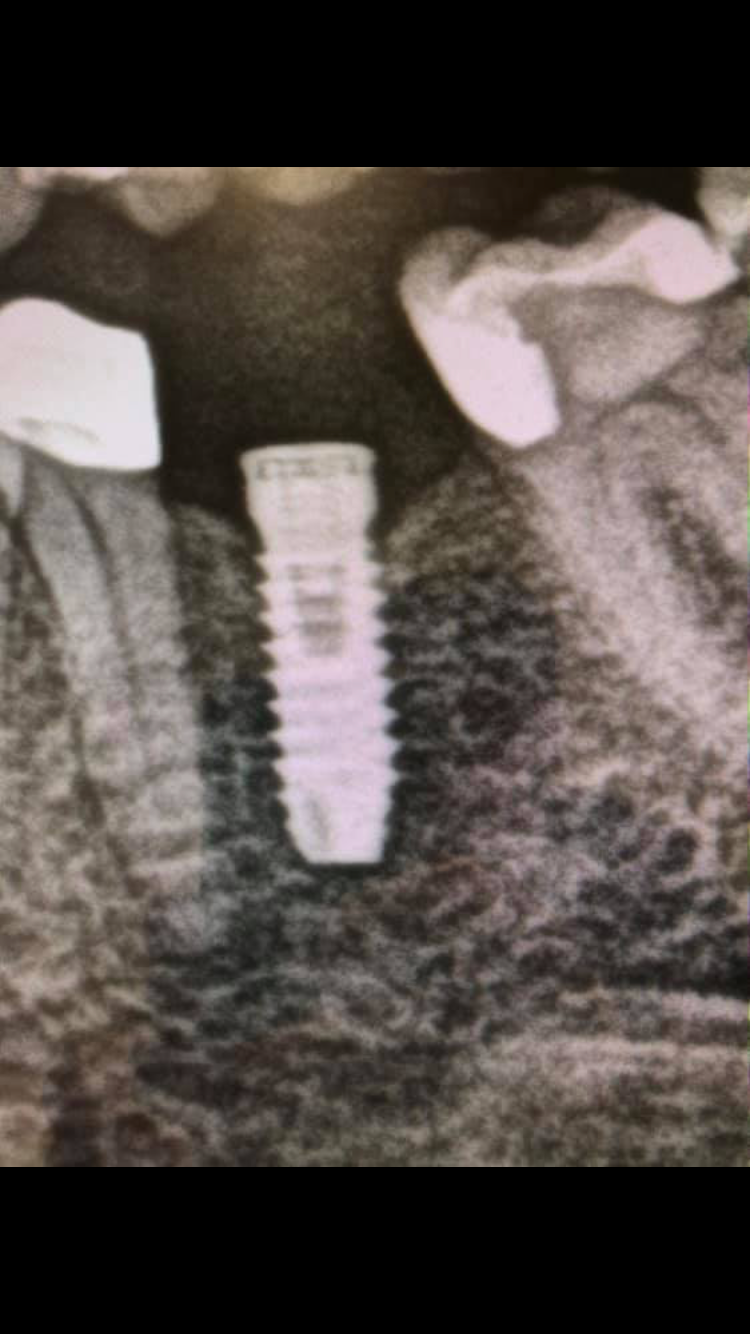

Estimados compañeros me podeis ayudar con la marca de implantes del 1 cuadrante? ,os adjunto una periapical y una imagen obtenida de la pano, 1 saludo y muchas gracias

Buenos días: Tengo una paciente que necesito rehabilitar pero desconoce marca del implante y medidas.A la paciente le suena que pueden ser marca Straumann Podéis ayudarme a saber marca y [...]

La paciente se realizó el implante en Francia hace 20 años y quiere cambiar La Corona. ¿Sabéis que marca es y diámetro? Y ¿ donde puedo conseguir transfer?. Gracias

Hola, es un implante monobloque, que se ha colocado hacer 15 años, no es imbiodent. Alguien que sepa de qué casa comercial es?? Muchas gracias

buenas tardes. tengo este caso y necesito saber los aditamentos posibles compatibles. podrían echarme una mano? adjunto foto de la pegatina,pano y periapical un saludo y gracias